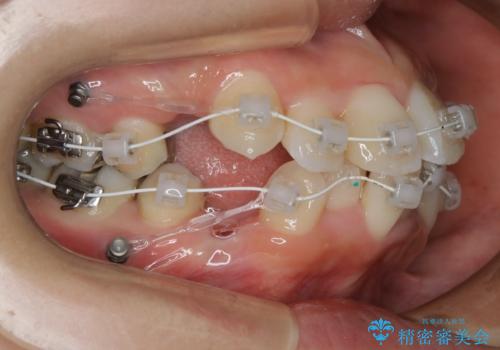

- ワイヤー審美装置

- 治療期間

- 2年

- 歯のガタつきと出っ歯が気になるので矯正治療を希望し来院された患者様です。

上下顎とも歯を並べられるスペースが無く、口元を下げたいというご希望だったので、抜歯とワイヤー矯正を併用した治療を計画しました。

抜歯スペースを利用し口元を大きく下げることが出来ました。